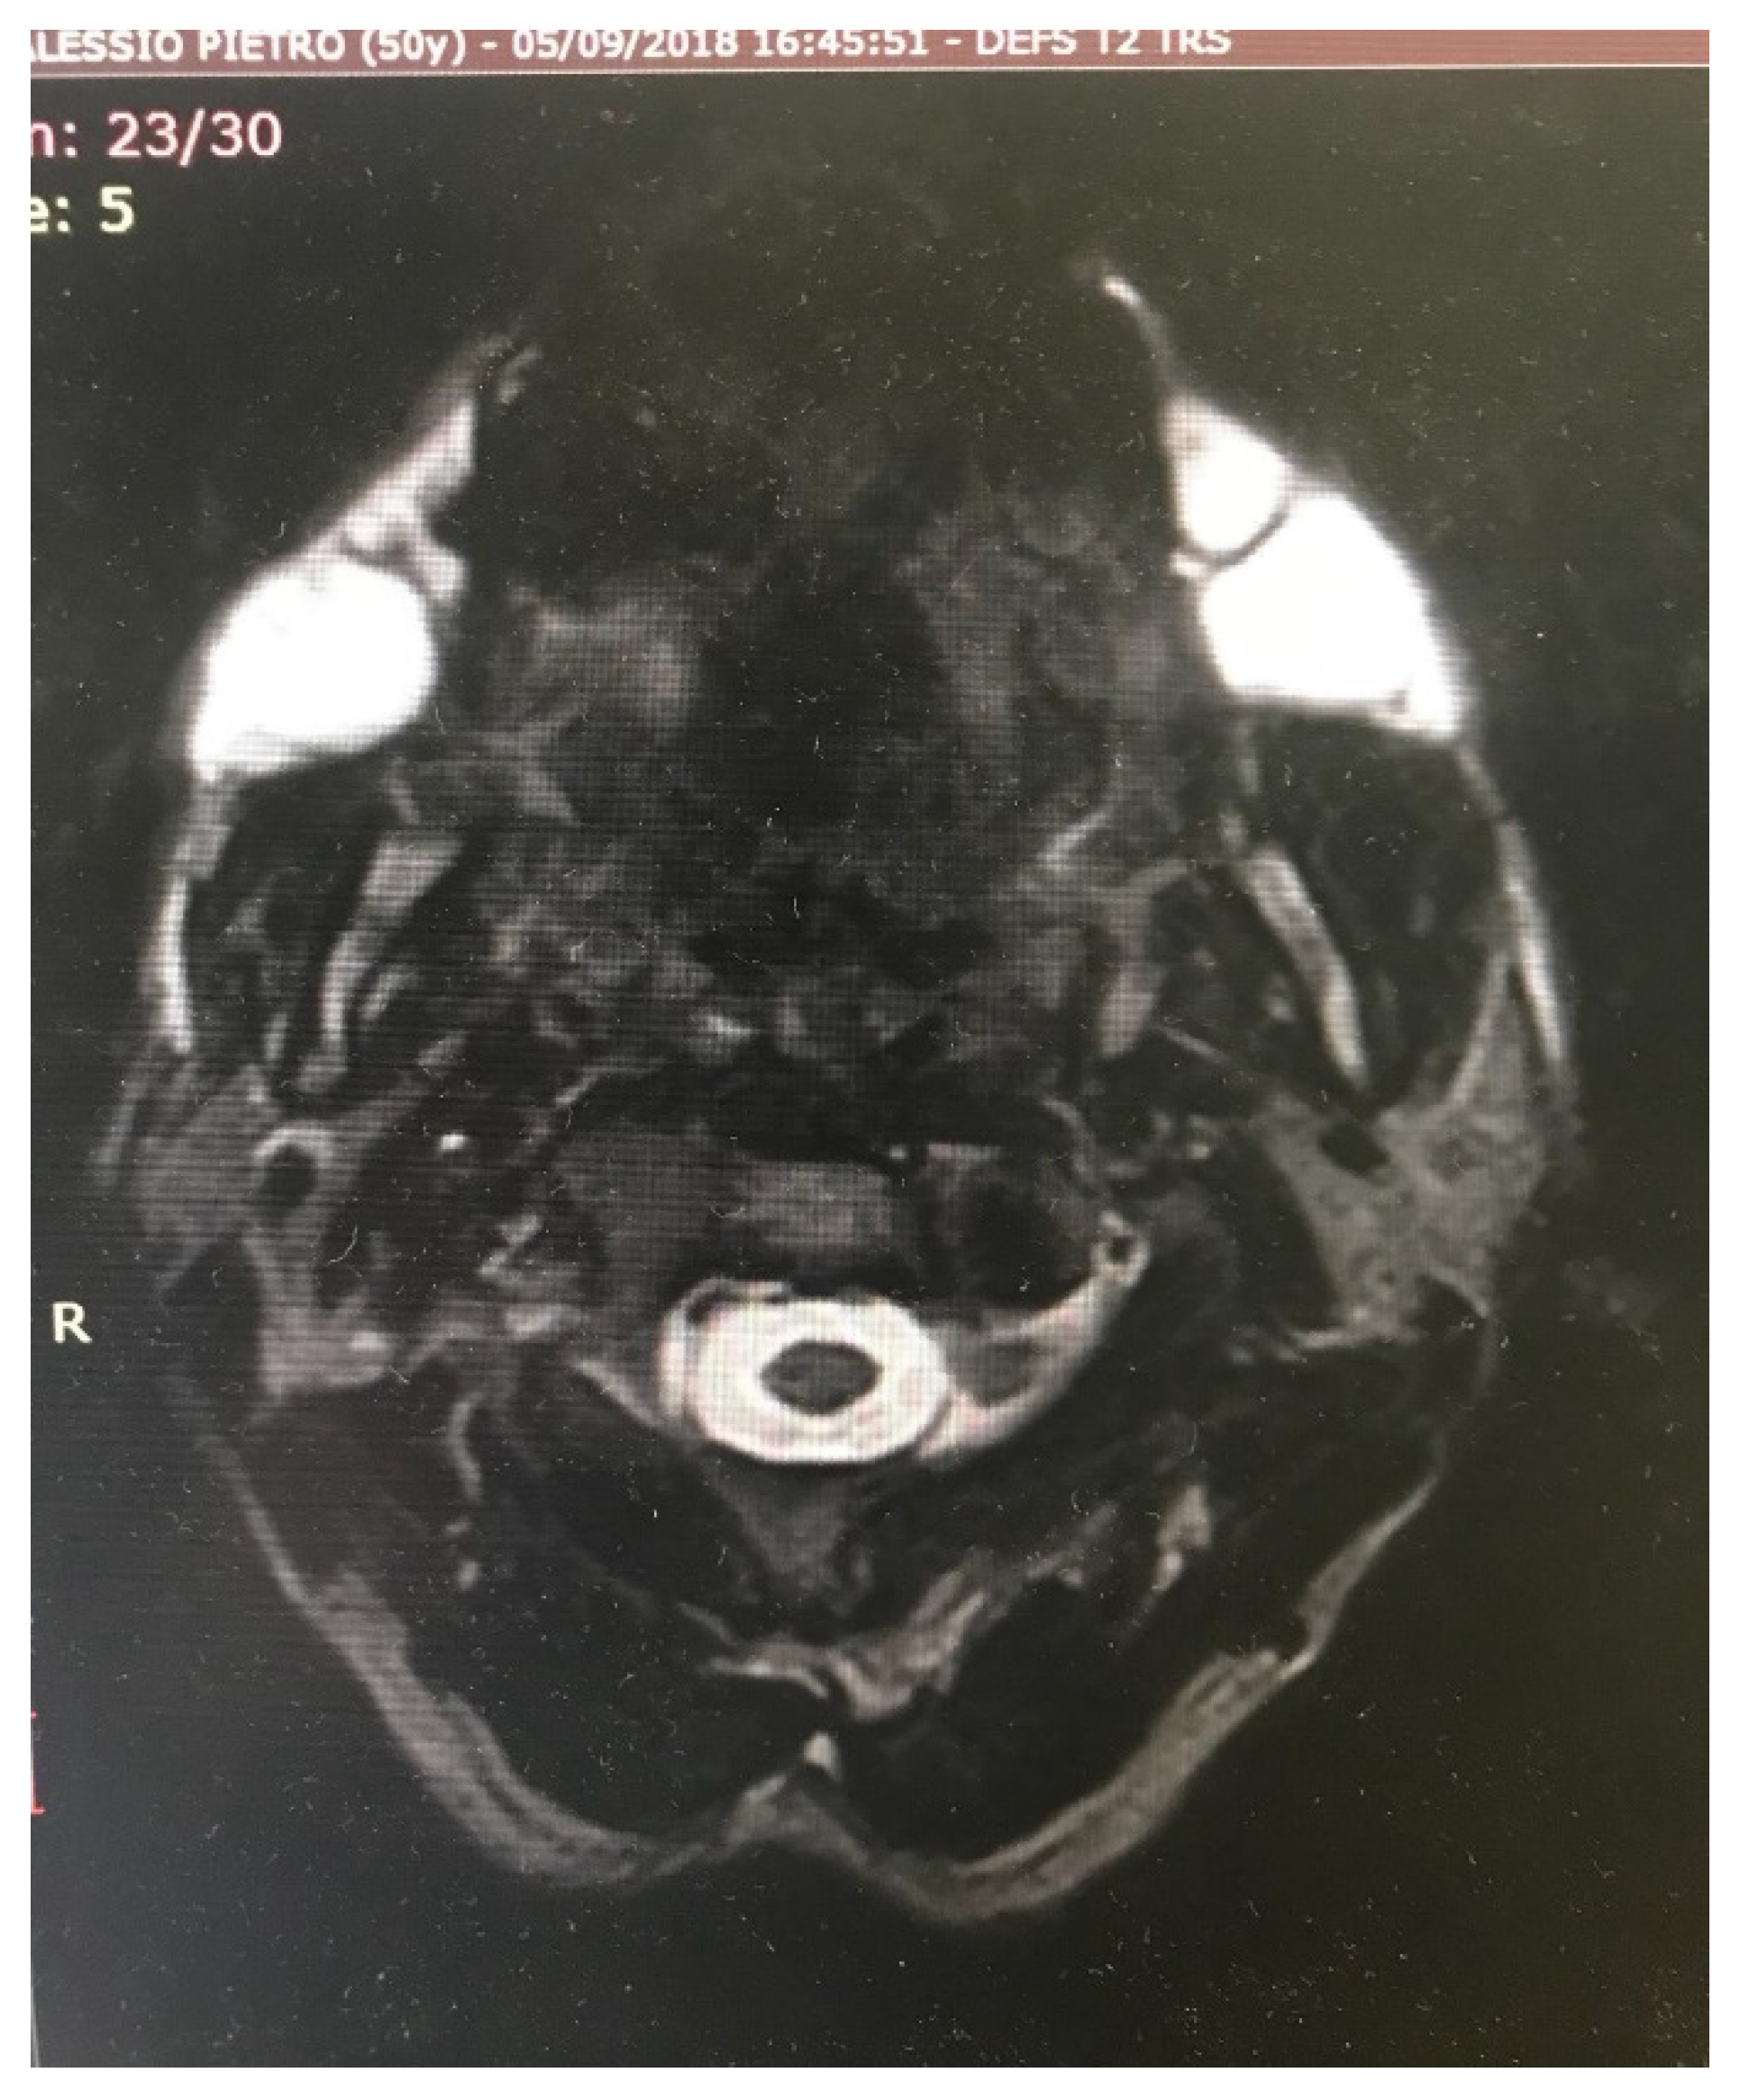

Figure 8.

Bilateral huge abscess in a patient receiving polyacrylamide hydrogel injections 10 years after treatment.

Figure 9.

Magnetic Resonance Imaging (MRI) of bilateral huge abscess in a patient (the same patient shown in Figure 8) receiving polyacrylamide hydrogel injections 10 years after the treatment.

Figure 10.

MRI of Caucasian male patient from Figure 8 showing bilateral collection of semi-fluid material.

Patients receiving HA and DCA injections did not experience other complications. In a patient receiving CaHA, tardive huge swelling developed 3 weeks after the injections and the clinical situation was resolved after 3 days of oral corticosteroid therapy. Patients receiving polyacrylamide hydrogel injections showed small, palpable, nonvisible nodules in 13 cases in the first 5 years of follow up; after that period, most of the patients were lost for follow up. Two patients experienced gel induration after 8 years: one of them developed an aseptic abscess requiring drainage (Table 2). One more patient developed a huge abscess requiring surgical drainage 10 years after the injections (Figure 8, Figure 9 and Figure 10).